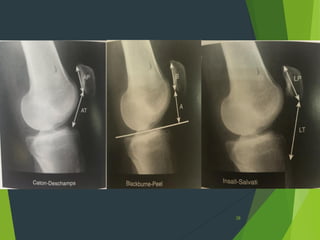

Patella alta

 Blumensaate line

 Insall ratio  1.2

 Blackburne 1.06

 caton-Deschamps  1.3